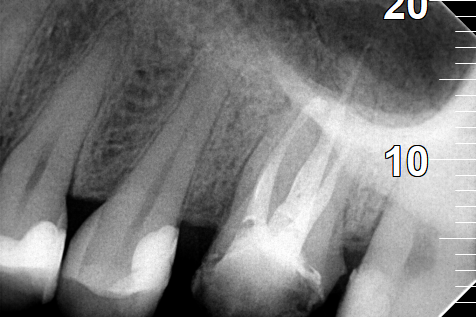

Ο ασθενής στο πλαίσιο της ολικής αποκατάστασης του στόματος του αποφάσισε την επανάληψη απονευρώσεων των δύο γομφίων στη δεξιά πλευρά της άνω γνάθου. Μετά την ολοκλήρωση των νέων απονευρώσεων τα δόντια αποκαταστάθηκαν με νέες ολοκεραμικές στεφάνες ζιρκονίου δοντιών.

Παλιές απονευρώσεις των δύο άνω δεξιών γομφίων

Νέα απονεύρωση στον άνω πρώτο δεξιό γομφίο

Αφαίρεση όλης της παλιάς απονεύρωσης στον άνω δεύτερο δεξιό γομφίο

Νέα απονεύρωση στον άνω δεύτερο δεξιό γομφίο